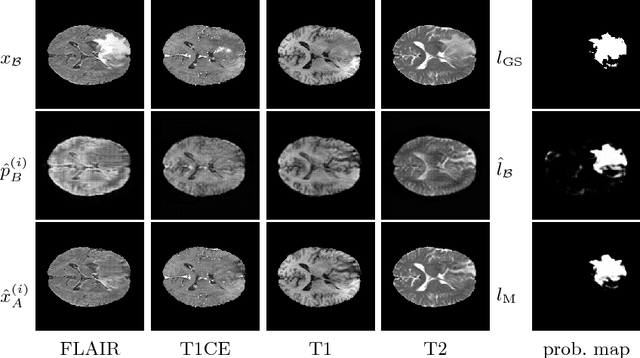

Abstract:We present a method to model pathologies in medical data, trained on data labelled on the image level as healthy or containing a visual defect. Our model not only allows us to create pixelwise semantic segmentations, it is also able to create inpaintings for the segmentations to render the pathological image healthy. Furthermore, we can draw new unseen pathology samples from this model based on the distribution in the data. We show quantitatively, that our method is able to segment pathologies with a surprising accuracy and show qualitative results of both the segmentations and inpaintings. A comparison with a supervised segmentation method indicates, that the accuracy of our proposed weakly-supervised segmentation is nevertheless quite close.